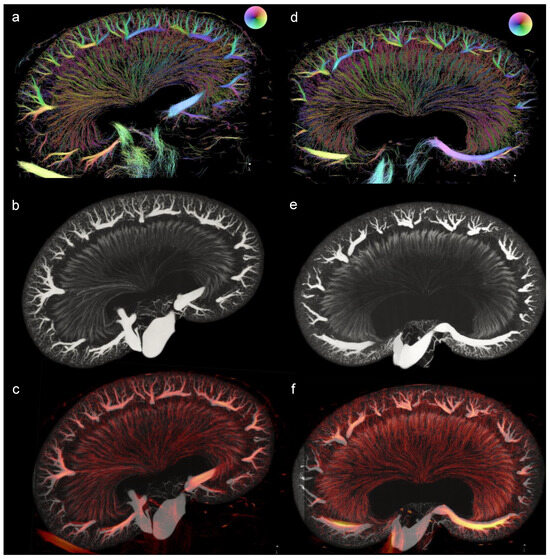

Figure 11.

Visual comparison between the µCT and SRUS images. (a–c) displays the kidney from a lean Zucker rat and (d–f) the kidney from a Zucker diabetic fatty rat, both at 22 weeks of age. (a,d) shows the SRUS images, (b,e) the µCT images (maximum intensity projection of 33 slices), and (c,f) displays the overlay of the two different modalities. The image slices from the µCT volume were found using Tomviz (version 1.9.0). Due to the transformation of the structure from in vivo to ex vivo, the SRUS images were scaled to match the µCT image in the following way: 50% transparency was used on the intensity of the SRUS image, image (c)’s image was rotated 3.45 degrees to the right, increased 5.7% in height, and decreased 3.6% in length. (f) was increased 2% in height and decreased 11.5% in length.

A good correspondence between the SRUS and the µCT was found in one kidney from a ZDF rat and one kidney from an LZR, after a coarse manual alignment with a maximum of 11.5% scaling (Figure 11). For example, both imaging modalities clearly displayed the cortical radial arteries as well as the vasa recta in the medulla.